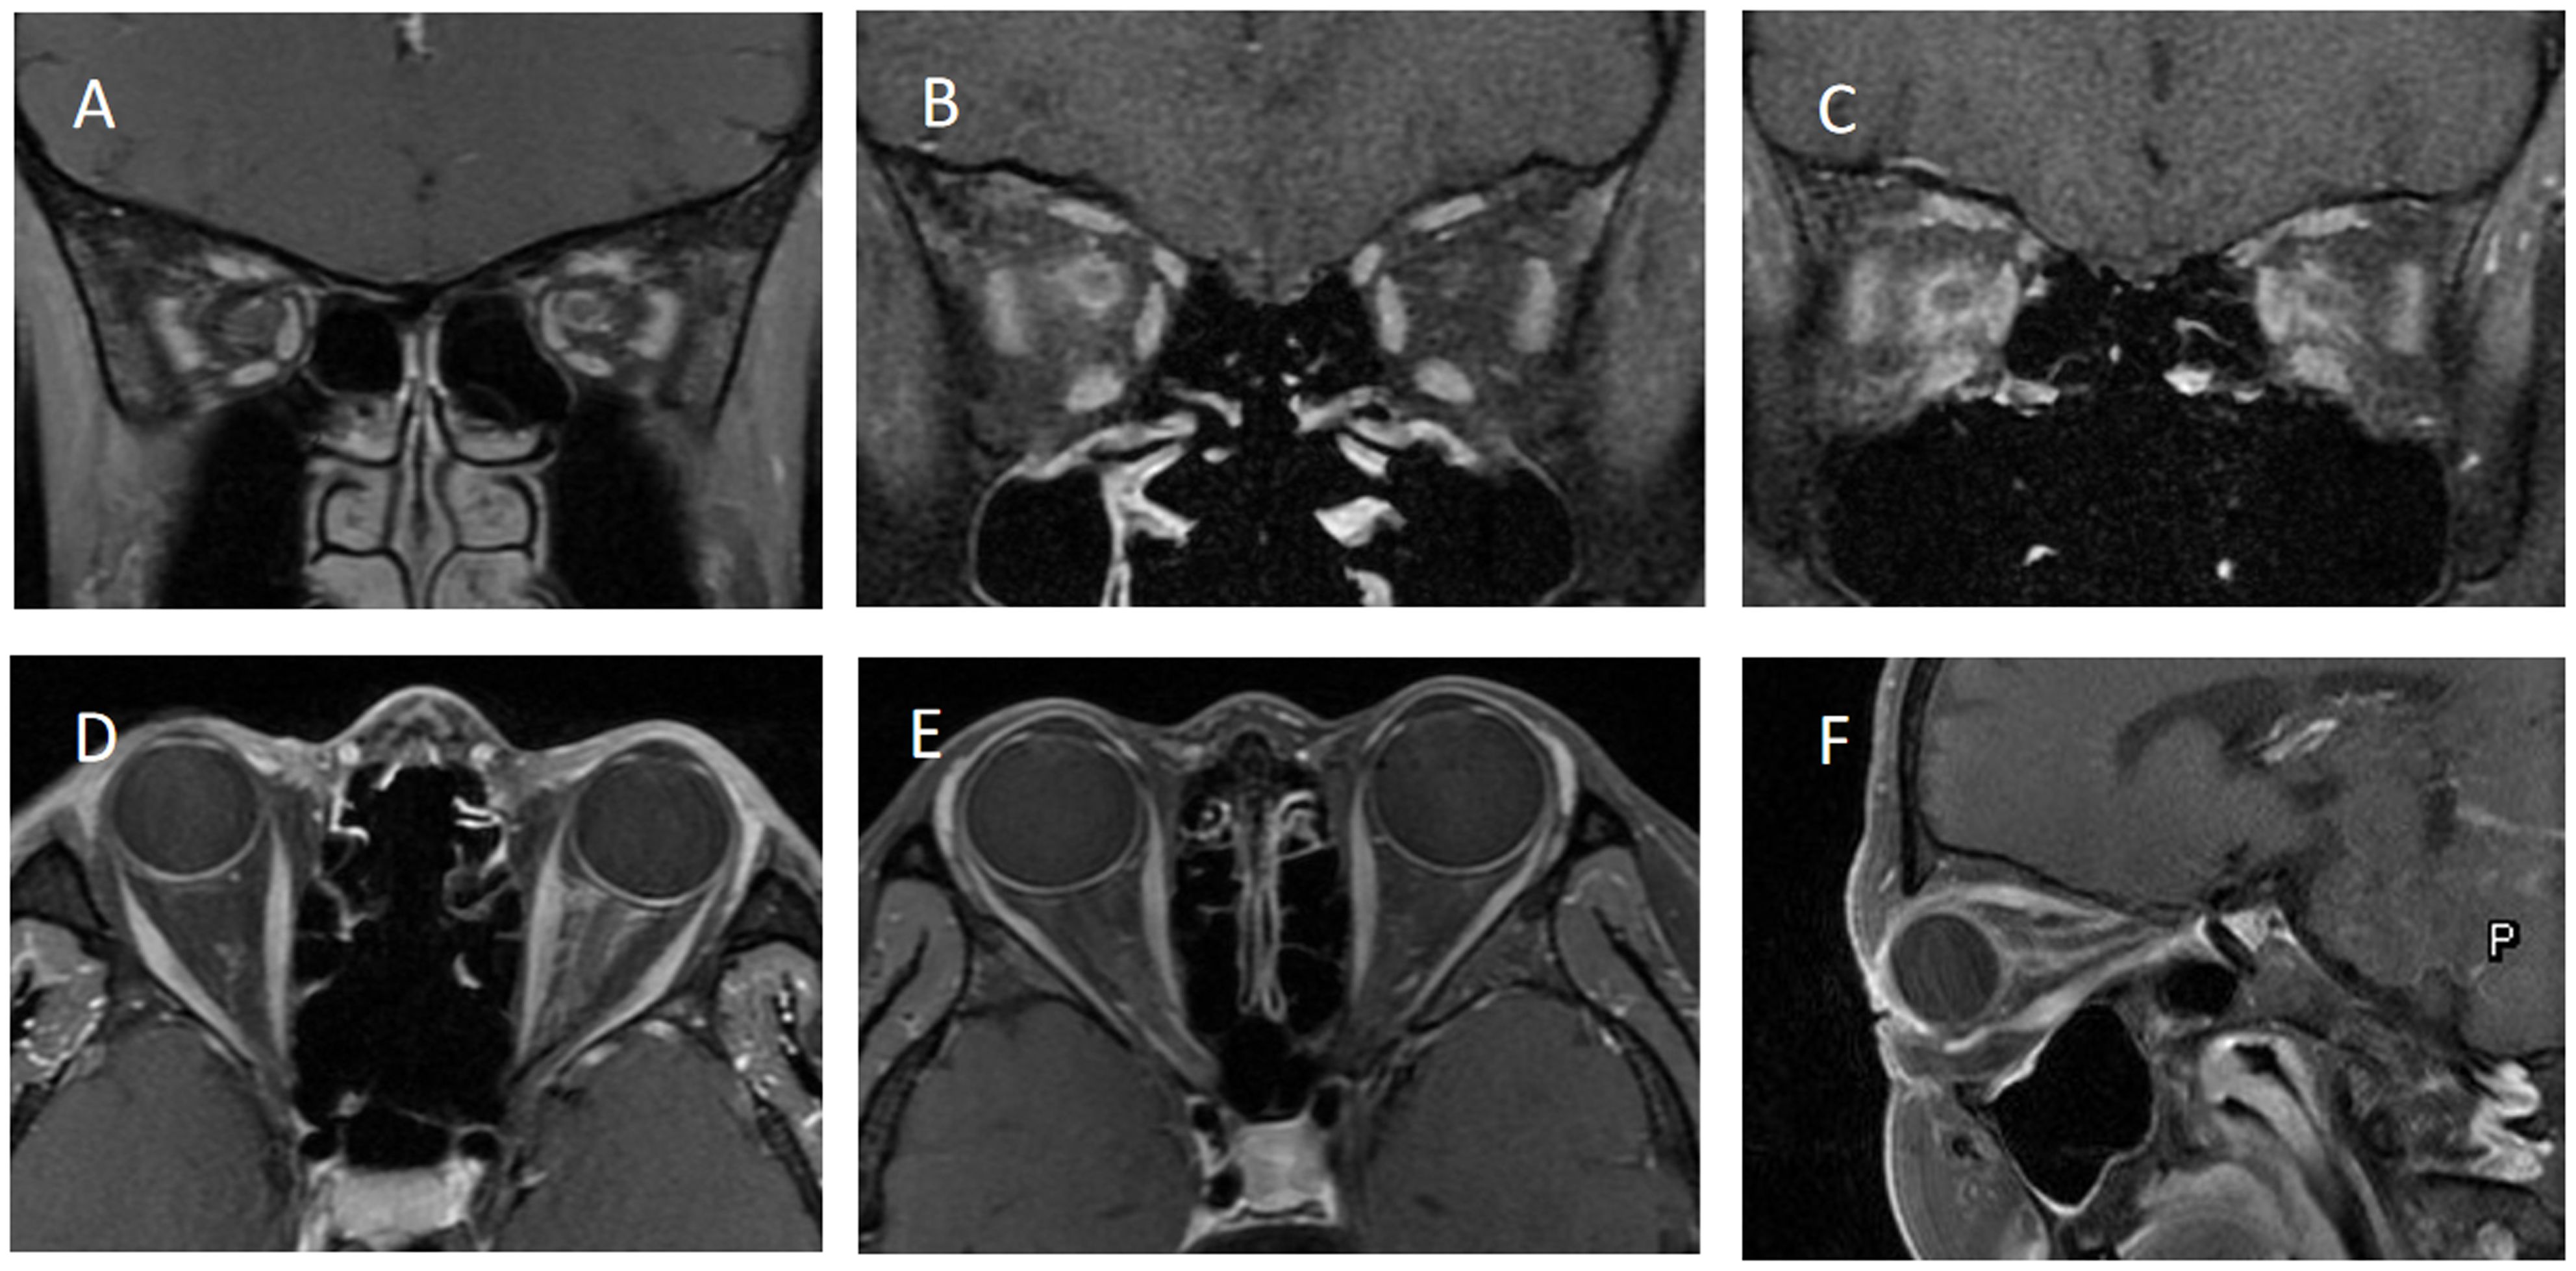

Table 1 provides a comprehensive overview of the demographic and clinical characteristics of MOG-ON cases at the time of onset. This study evaluated a total of 33 patients (44 eyes), with 24.2% testing positive for MOG-IgG in their serum, including 8 cases (24.2%) of MOG-OPN and 25 cases (33.3%) of Seronegative OPN; The average age of onset of OPN in this study cohort was 32.73 ± 18.61 years (age range 6–79 years), of which 24 cases (72.7%) were adults (≥ 18 years) (Figure 1A), 22 cases (66.7%) were females, 11 cases (33.3%) showed bilateral involvement, 24 cases (72.7%) had eye pain and 25 cases (75.8%) had optic disc swelling at the first onset, 7 cases (21.2%) had a fever or respiratory infections before the onset of OPN. The average time from onset to the worst vision was 8.33 ± 4.29 days. 32 patients (97.0%) had different visual field abnormalities. All patients showed ONS enhancement in orbital MRI, and Figure 2 showed the classic ONS enhancement in different patients.

Figure 2

Six MRI images labeled A to F showing various cross-sectional views of the sinus and orbital regions. Images A to C are coronal views, while D to F are axial and sagittal views, illustrating anatomical structures and potential abnormalities.

Figure 2. shows the orbital MRI of different optic perineuritis (OPN) patients. (A) The coronal T1 contrast image showed enhancement of the left optic nerve sheath (ONS). (B) Coronal T1 contrast image showed enhancement of the right ONS (C) Coronal T1 contrast image showed enhancement of both ONS. (D) Axial T1 contrast image showed enhancement of left ONS. (E) Axial T1 contrast image showed enhancement of right ONS. (F) The sagittal T1 contrast image showed left ONS.